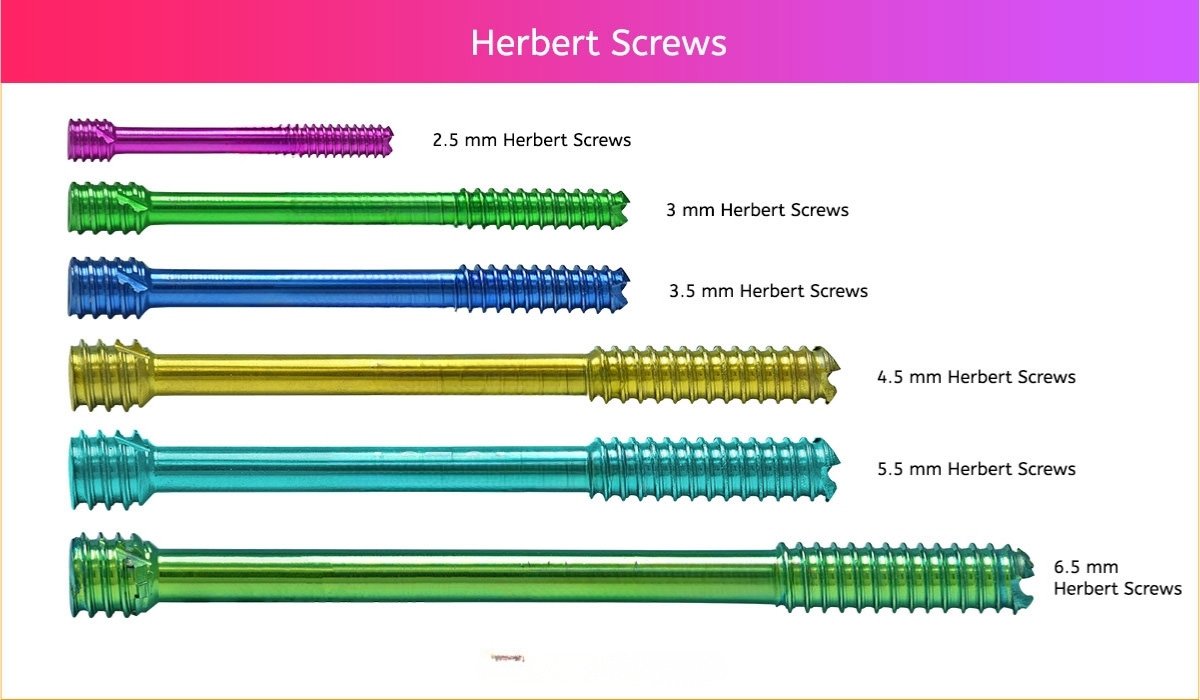

2.5 mm Herbert Screw

3 mm Herbert Screw

3.5 mm Herbert Screw

4.5 mm Herbert Screw

5.5 mm Herbert Screw

6.5 mm Herbert Screw